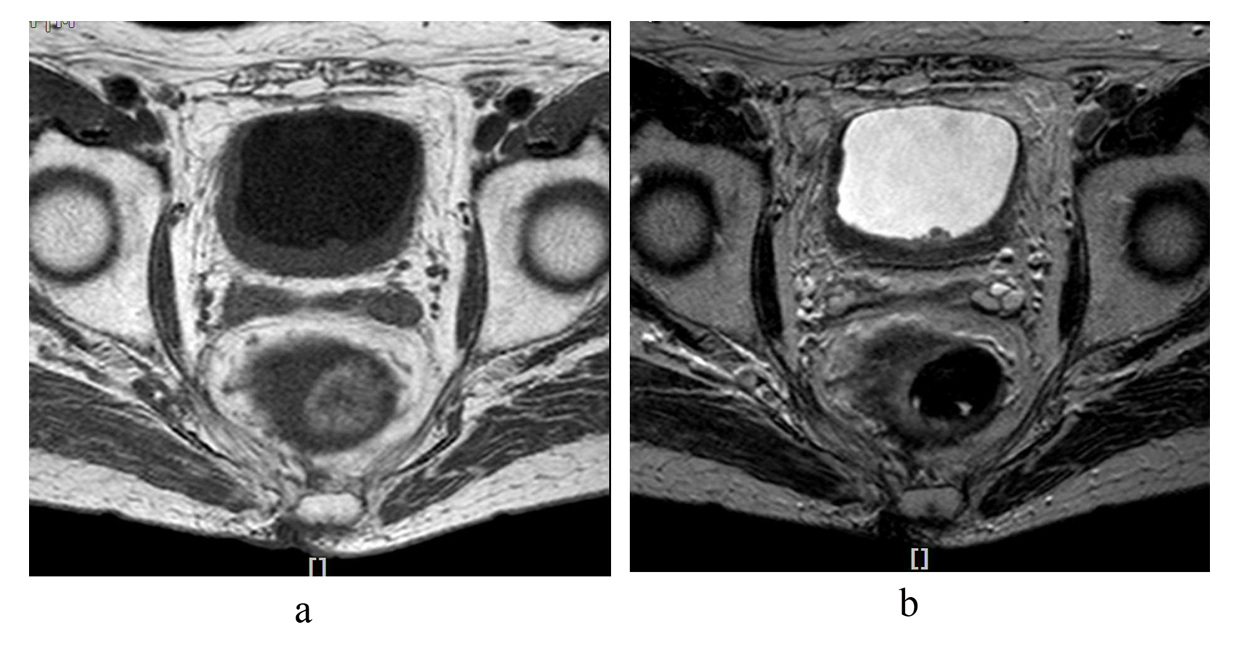

A 79-year-old Japanese man was referred to our department because of an elevated serum prostate-specific antigen (PSA) value. He had no past medical history, except for radiation exposure from an atomic bombing. When the atomic bomb was detonated over Hiroshima on August 6, 1945, he was within a wooden construction located 1.7 km from ground zero and exposed to about 0.072 Gy of ionizing radiation as DS02 urinary bladder organ dose [3]. He was diagnosed with stage pT2bN0M0 prostate cancer. A pathology examination showed a moderately differentiated adenocarcinoma. His Gleason score was 4 + 3 = 7. He underwent combined androgen blockade therapy. One year after initiating this therapy, asymptomatic gross hematuria was present, although his serum PSA value had already fallen below the detectable limit. Magnetic resonance imaging depicted diffuse thickening of the urinary bladder (Fig. 1). Cystoscopy showed that multiple sessile tumors had developed from the posterior and bilateral walls of the bladder. A pathological analysis of the biopsy specimens revealed that tumor cells had infiltrated from the mucosa into the lamina propria. The cells were crescent-shaped with their nuclei compressed to one edge and a vacuole (Fig. 2). Further examinations, which included gastrointestinal fiberscopy, ruled out the possibility of SRCC of the gastrointestinal tract. Therefore, the tumor was diagnosed as being of bladder origin. The tumor was organ-confined at that time. However, he refused any excessive therapy such as intravenous anticancer chemotherapy or cystectomy because of his advanced age. The oral administration of tegafur-uracil (200 mg/m2 per day) was initiated. Six months later, his serum CA 19-9 value - which is a reliable test for SRCC activity - had declined to 35.8 U/mL from 42.9 U/mL (The normal range is less than 37 U/mL). However, 12 months after the start of this treatment, his CA 19-9 value gradually increased and finally reached 109.7 U/mL. He had severe normocytic and normochromic anemia and rapid deterioration of renal function. Computed tomography (CT) demonstrated that the distal ends of both ureters were involved in the tumor, which had infiltrated the whole bladder and resulted in postrenal azotemia. A percutaneous nephrostomy was immediately placed in the right renal pelvis. He was administered palliative care. He died in March 2013 because of cancerous cachexia.

![]() Click for large image | Figure 1. (a). T1- and (b). T2-weighted magnetic resonance imaging shows thickening of the posterior and bilateral walls of the bladder. |